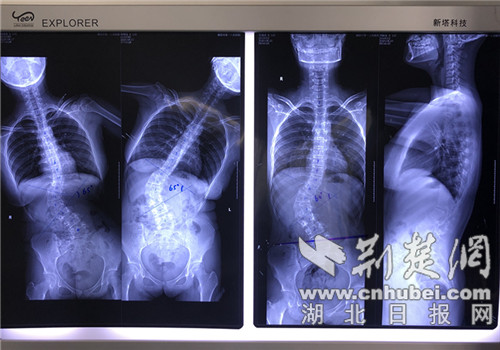

台积电优势,台湾积体电路半导体核心技术,荆楚网客户端—荆楚网消息(记者向乔丹 通讯员乔盟林、郑勇玲)8月27日,记者从襄阳市第一人民医院获悉,该院骨科一区最近收治了两名青少年患者,他们都被诊断为脊柱侧弯。  据了解,13岁的小宇跟大多数同龄孩子一样爱玩爱闹,平时胃口好又不爱运动,体重已达113公...